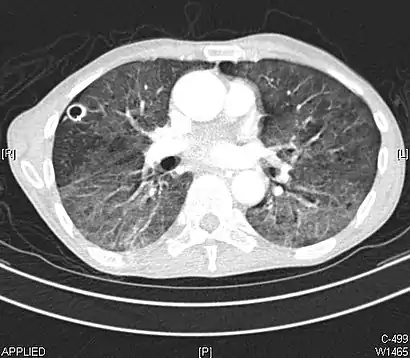

High-Resolution CT image in a patient with Pneumocystis pneumonia infection showing ground-glass opacities.